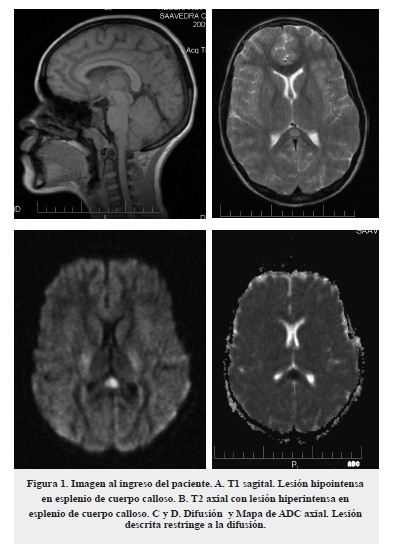

Se administró tratamiento con aciclovir por 14 días e inmunoglobulina a dosis total de 2 gr/kg dividida en dos dosis. Se realizó una punción lumbar de control al tercer día con disminución de parámetros inflamatorios. En la evolución clínica se encontró resolución total de los síntomas a las 4 semanas, con RMN cerebral de control al mes y al año del inicio del cuadro dentro de límites normales (figura 2).

En estudios imagenológicos de esta entidad se aprecian lesiones hipointensas en T1, hiperintensas en T2 y que restringen en difusión en mapa de ADC, las cuales involucran en todos los casos el esplenio del cuerpo calloso. Se ha subclasificado la entidad en MERS tipo1 y tipo 2 según la extensión de la lesión, en el primer caso la lesión está circunscrita al esplenio del cuerpo calloso, mientras que, en el segundo puede extenderse a lo largo de todo el cuerpo calloso y a la sustancia blanca extracallosal, principalmente frontoparietal. De estos dos patrones el primero es de mejor pronóstico1,2.